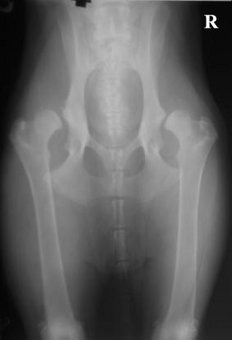

Erke, va palygink su savo. 1 sveikas, 2 sunkus laipsnis, 3 kaire...

(2 foto iš 3)